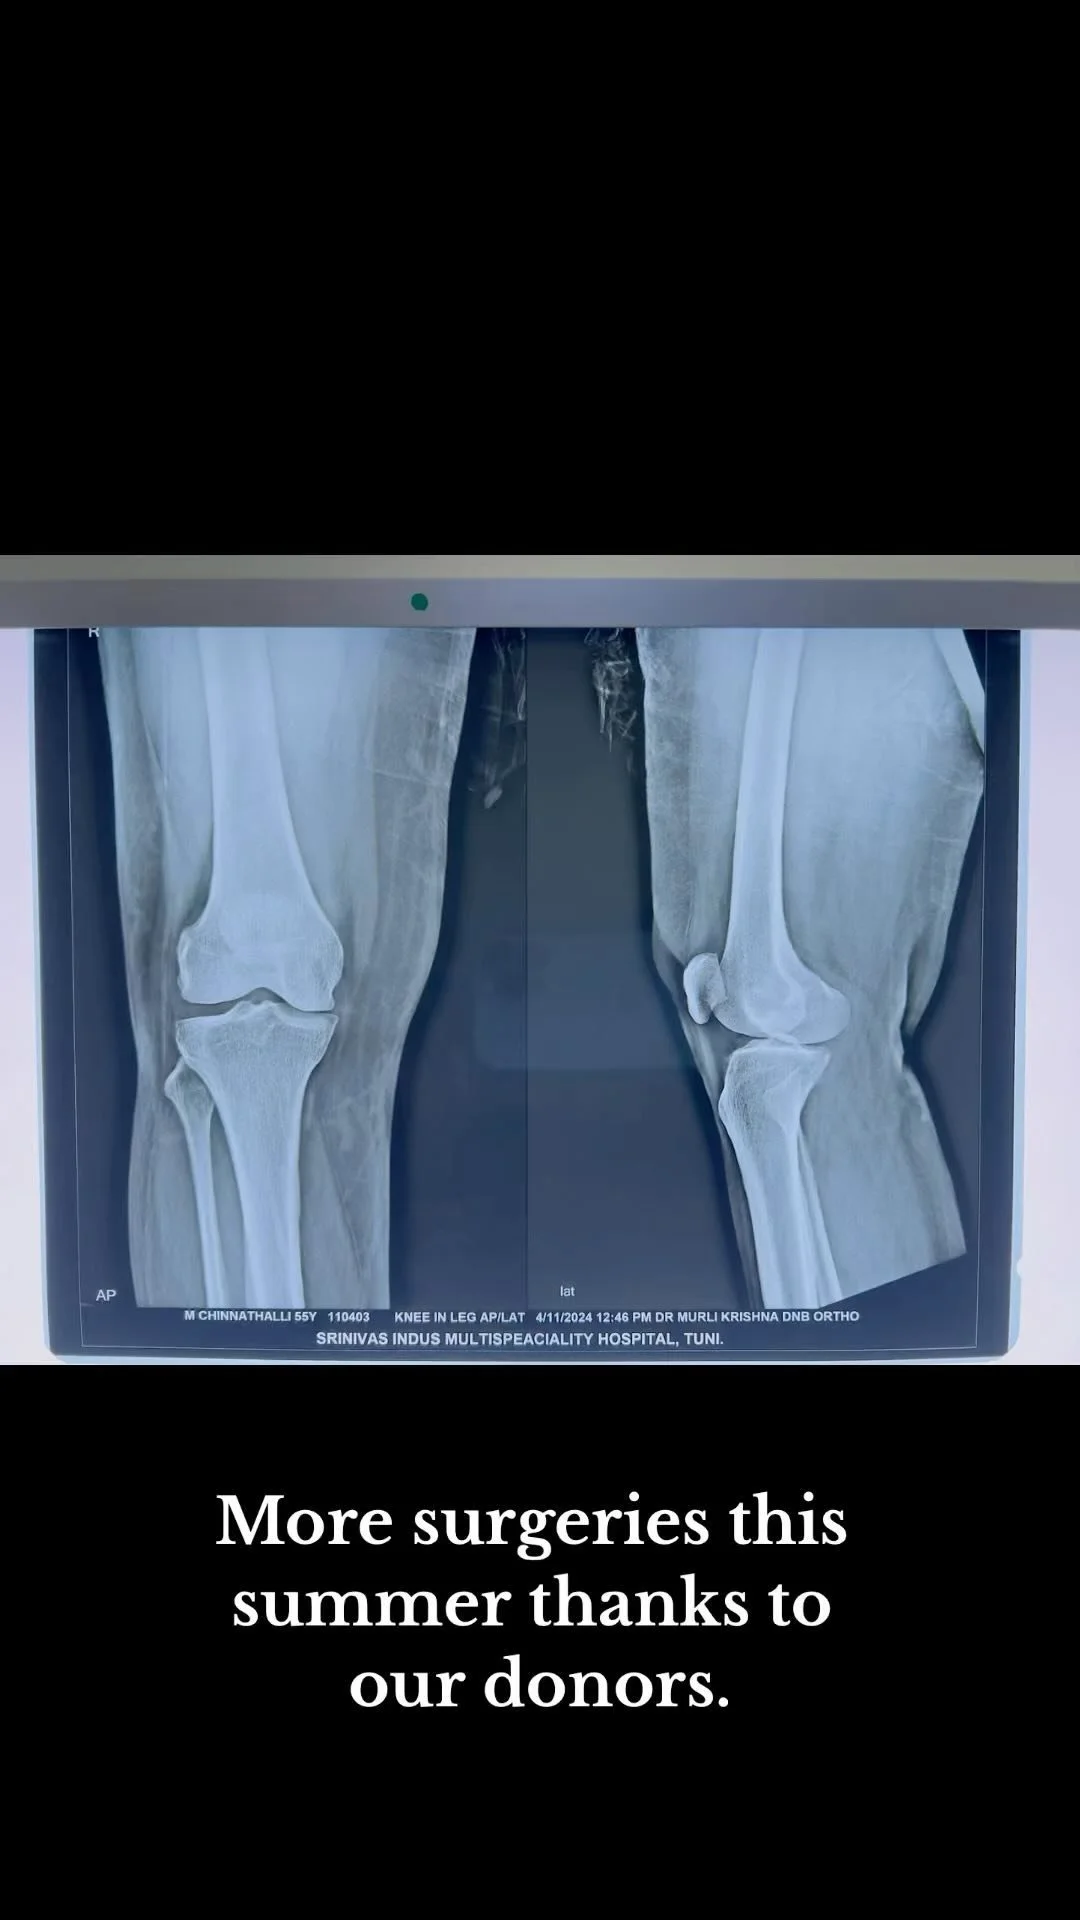

Supporting joint replacement surgeries and medical education. Since starting in 2023, we have come so far⦠View fullsize View fullsize View fullsize View fullsize View fullsize View fullsize View fullsize View fullsize View fullsize View fullsize View fullsize View fullsize